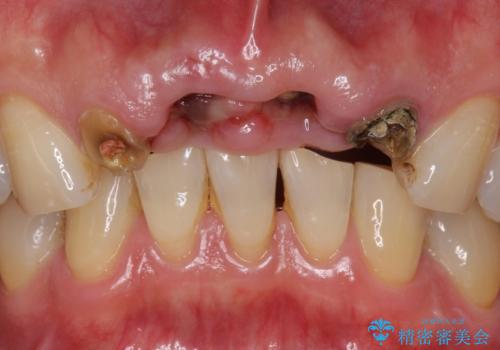

- お風呂場で転んで上の前歯が2本抜けてしまったことを主訴に来院された患者様です。

精査したところ、左上の側切歯(左上2)も破折しており保存不可能な状態でした。

左上の側切歯(左上2)を抜去し、右上の側切歯(右上2)の再根管治療後、セラミックのブリッジによる補綴を行いました。